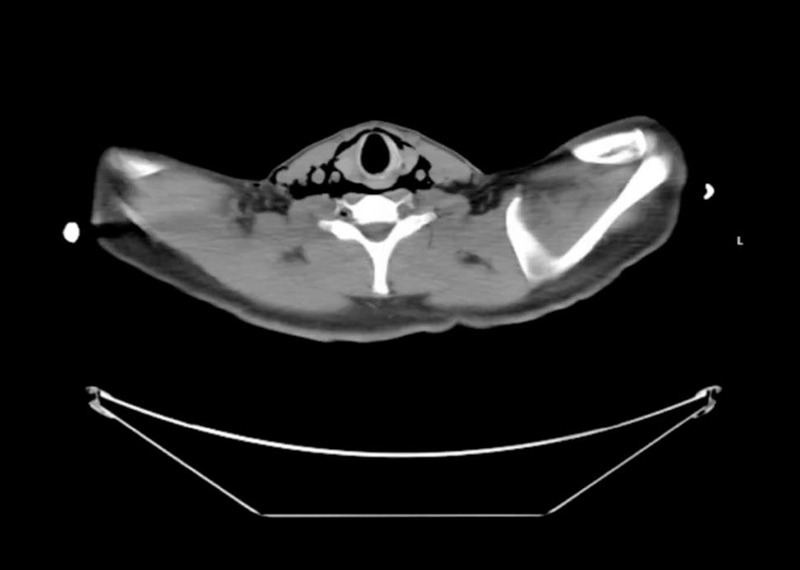

Figure 3

Figure 3. CT esophagography shows the retropharyngeal soft tissues dissecting through the myofascial plane, which communicate with the soft tissues of the base of the neck and supraclavicular region.